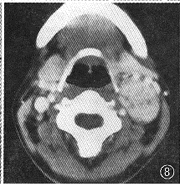

1.肿瘤CT增强影像表现特殊,可分为以下几类:(1)低密度区中伴团状高密度改变24个(图1),病理改变为在比较广泛分布的疏细胞区(Antoni B区)组织中,有相对集中分布的富细胞区(Antoni A区)(图2)。(2)弥漫点状改变20个,点状大小从1~4 mm不等,其密度不等。高密度CT值为60~80 HU,低密度为40~45 HU,两者CT值相差约20 HU。其中呈低密度点状4个;高密度点状4个;高、低密度混杂点状12个(图3)。此20个肿瘤中8个伴有1~2个形态不规则的低密度裂隙样变。高低密度混杂点状分布的病理改变为的Antoni A区、Antoni B区相互交错,分布均匀(图4)。低密度点状改变为比较广泛分布的Antoni A区或胶原基础上出现的零星分布的Antoni B区或微囊集中处,Antomi B区或微囊分布较集中时,即表现为低密度裂隙样改变。较广泛分布的Antoni B区伴少量Antoni A区或胶原则呈高密度点状改变。(3)低密度环伴中央弥漫不同密度点状改变5个,其中单纯为低密度点状或单纯为高密度点状各1个。此低密度环在病理上由Antoni B区组成。(4)中央低密度伴有环形改变8个(图5),环壁厚,环表现各异,其中表现为高、低密度混杂点状分布的3个,单纯低密度点状或高密度点状各2个,环与肌肉呈等密度1个。肿瘤中央的低密度区病理上由Antoni B集中区和(或)陈旧性出血区组成。(5)密度均匀的12个肿瘤中,等密度与低密度各5个,囊性变2个。在病理上等密度多由Antoni A区及胶原组成,Antoni B区较少,分散在Antoni A区及胶原间;而低密度肿瘤(图6)为均匀一致的Antoni B区及部分陈旧性出血组成,几乎无Antoni A区细胞(图7)。囊性肿瘤巨检时见黄色液体流出,囊壁上仍见典型Antoni A、Antoni B区改变。(6)增强特别明显的肿瘤3个,其中2个为弥漫点状改变(图8),1个为厚环。病理显示此3个肿瘤由丰富的Antoni A区组成,夹杂有微囊,而Antoni B区少见(图9),其中仅2个血供比较丰富。

图8 左颈神经鞘瘤增强扫描,示明显强化,伴有小的低密度点状改变

图9 图8肿瘤病理学(HE ×40)表现,示肿瘤主要为Antoni A区,CT所示点状低密度区为微囊(黑箭)及陈旧性出血(空箭)